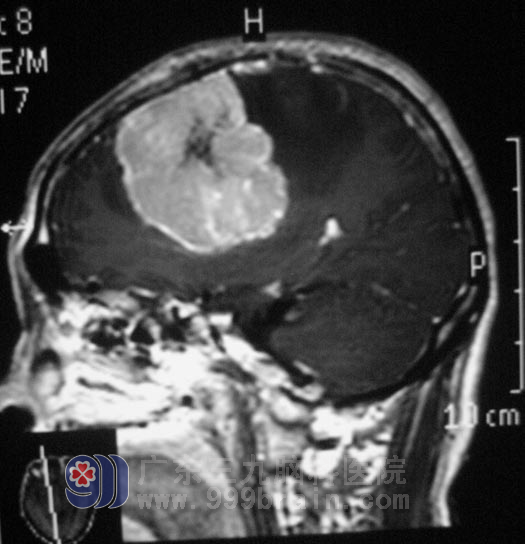

叶叔转至广东三九脑科医院时,已无法自行坐立、行走,双侧眶周轻度肿胀,语言欠流畅,反应、理解能力变差,左侧肢体活动差,轻瘫试验阳性,左侧躯体、肢体痛温觉减弱。头部MRI结果显示:右侧额顶部大脑镰旁窦旁占位,考虑脑膜瘤可能性大,右侧颞叶钩回疝及大脑镰下疝形成。影像见6.6×4.9×6.3cm大小不规则肿瘤影,边界清楚,周围可见“假包膜征”,相邻脑膜可见“脑膜尾征”。病灶向脑组织内突入,邻近顶枕叶、胼胝体、右侧侧脑室体后角受压、变窄。

肿瘤巨大侵及位置广泛,术前有明显高颅压及明显肢体运动功能障碍。手术难度大,术后易出现偏瘫、癫痫等并发症。家属反复考虑后同意行手术治疗。